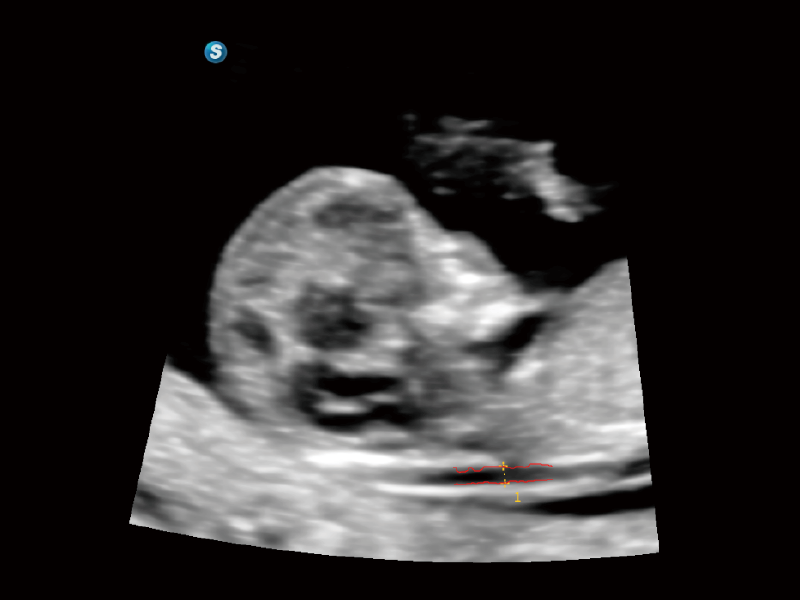

Image quality always lies at the core of definitive clinical outcomes. The P80 Elite introduces evolutional transducers with excellent 2D image clarity and color sensitivity for more confident assessment in anatomy and pathology.

S-Fetus 5.0